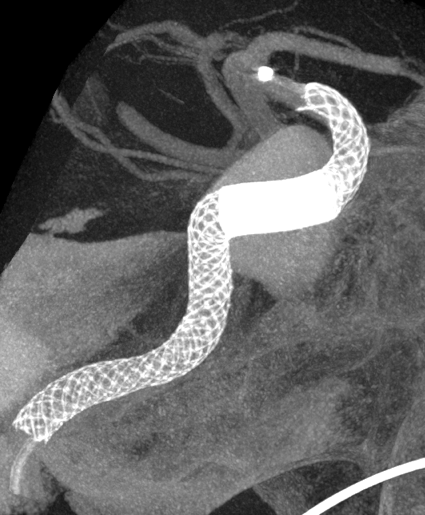

脳動脈瘤の新しい治療法「フローダイバーターステント」

脳動脈瘤に対する外科的治療は、従来頭を切って行う開頭クリッピング術に始まり、近年では血管内治療:カテーテルでの動脈瘤コイル塞栓術が進歩してきました。しかしコイル塞栓術は動脈瘤の形状、とくに動脈瘤の開口部(ネック)が広いものは、コイルが正常血管へ逸脱してしまい不向きとされていました。これに対してバルーンカテーテルでコイルが逸脱しないようにサポートする方や 、ステントというやわらかい金属を動脈瘤の入り口に留置し、コイルが正常血管に出てこないようにする方法が開発され、血管内治療の動脈瘤治療の適応が広がってきました。

ところが2015年に本邦においてフローダイバーターステント治療が導入されました。

動脈瘤内にコイルを充填することなく、非常に編み目を細かくしたステントで、これを正常血管に留置することで脳動脈瘤内に流入する血液量を減少させます。すると脳動脈瘤内の血液がうっ滞し、徐々に血栓化して脳動脈瘤が完全に閉塞します。半年後に約75%、1年後に約85%が完全に閉塞すると言われています。このような新しい治療法が動脈瘤治療において今後も期待されています。

Apoplexy 22

【フローダイバーダー留置】

Apoplexy 23

【半年後】

フローダイバーター治療の放射線学的画像